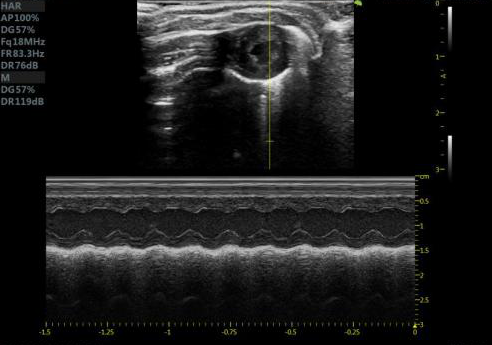

小鼠长轴M型 小鼠短轴M型

大鼠短轴M型 大鼠长轴M型